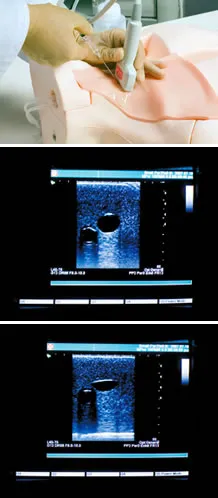

Skills & TrainingThree CVC approaches with landmark method:

Ultrasound guided CVC from internal jugular vein and axillary approach. Thorough procedure from puncture to cannulation Anatomical learning Complications indications: